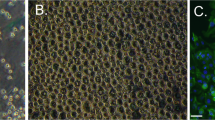

LPS is known to act through Toll-like receptor 4 (TLR4)38. To reveal the mechanism of urinary frequency induced by intravesical LPS instillation, we first investigated the TLR4 expression pattern in the bladder. To examine TLR4 expression in the urothelium, we performed immunohistochemical analysis combined with hematoxylin staining. Interestingly, strong immunoreactivity for TLR4 was observed on the apical side of the umbrella urothelium (Fig. 2a–d), which corroborates a previous report40. A specific expression pattern of TLR4 in the umbrella urothelium is indicative of its functional role against luminal bacterial LPS.

Specific expression pattern of TLR4 in the bladder urothelium. (a) Representative image of wild-type bladder stained with hematoxylin and eosin. (b–d) Immunohistochemical staining of TLR4 with hematoxylin counter-staining in the bladder of wild-type mice (b, c) and TLR4–/– mice (d). Panels in (c) show magnified views of boxed areas in (b). Arrows indicate TLR4 staining. Scale bars, 20 μm. At least three independent experiments were performed and similar results were obtained.